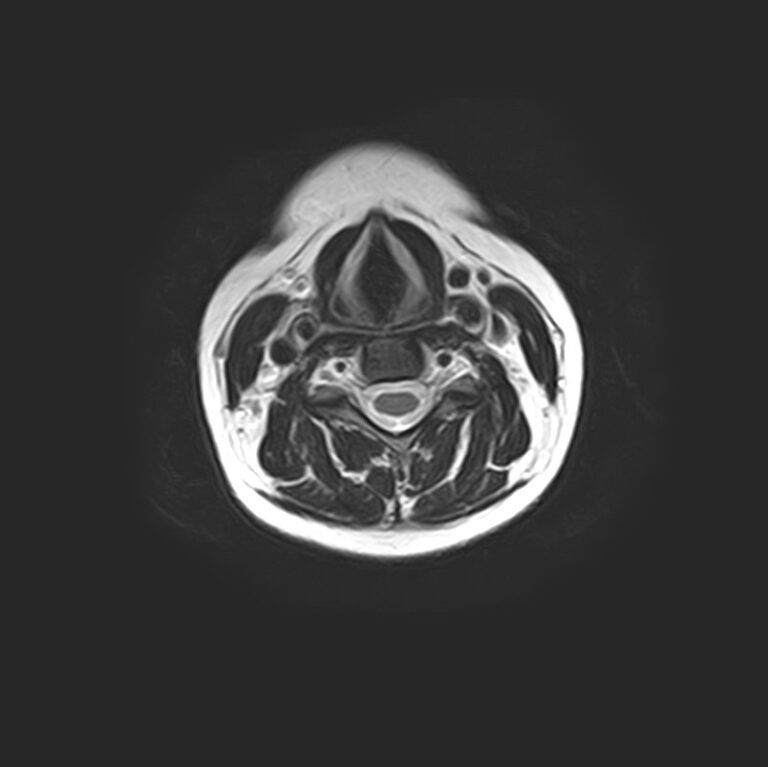

Для того, чтобы оценить состояние шейных позвонков с прилегающими тканями и одновременно визуализировать плечевой сустав, в нашей клинике выполняется комплексное обследование, включающее два протокола: МРТ шейного отдела позвоночника и МРТ плечевого сустава.

Метод МРТ позволяет оценить состояние всех анатомических областей шейного отдела позвоночника: костную структуру позвонков, спинной мозг с отходящими от него нервными корешками и окружающие мягкие ткани. Протокол обследования плечевого сустава включает оценку костной структуры, суставной капсулы, полости сустава с выстилающей его синовиальной оболочкой, связок, сухожилий, мышц и окружающих мягких тканей.